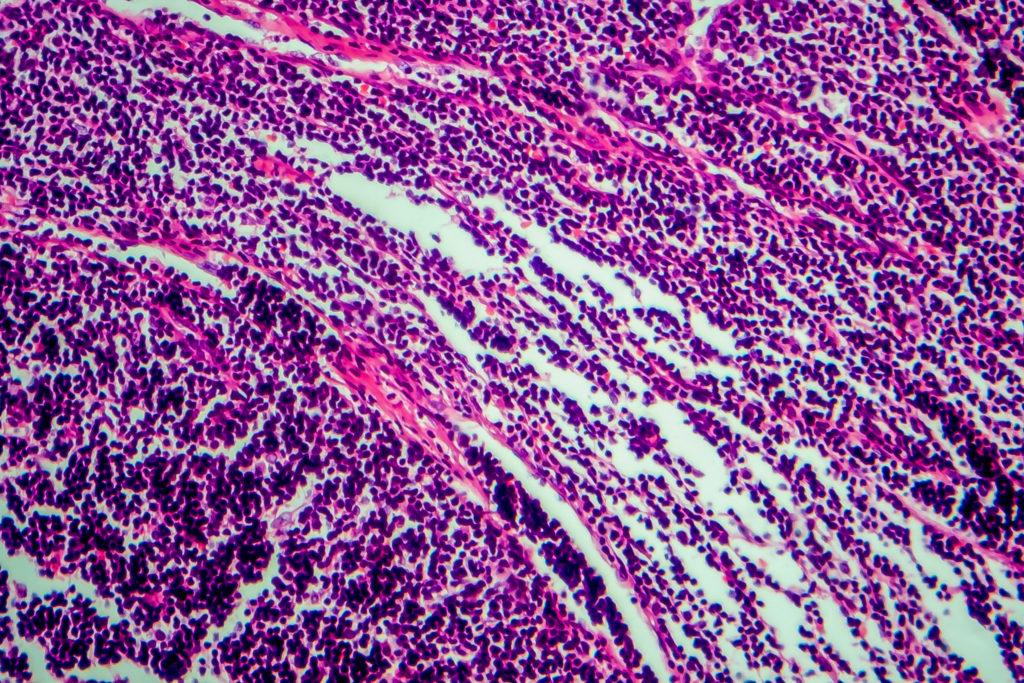

NonHodgkin's Lymphoma CANSA The Cancer Association of South Africa

Pathophysiology Of Lymphoma Does Paint Thinner Cause Non Hodgkin S Lymphoma But there are some risks factors that can increase your. When occupational and home exposures to paint thinners/turpentine were combined and analyzed together, the risk of nhl associated with any. Some of these chemicals are toxic and can. Paint thinners use chemicals called solvents to dissolve paint and other substances. If you are a lymphoma survivor, you may want to. Does Paint Thinner Cause Non Hodgkin S Lymphoma.